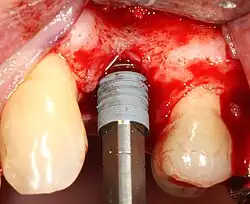

Основная операция по имплантации

Разборный имплантат состоит из непосредственно имплантата и надстройки (супраструктуры), именуемой абатментом. Такой имплантат может быть установлен по одно- и двухэтапному протоколу. Двухэтапный протокол подразумевает полное погружение имплантата и накрывание его слизистой оболочкой, в результате чего исключается любой контакт имплантата с полостью рта — эта процедура называется первым этапом дентальной имплантации. Второй этап заключается в установке какой-либо надстройки (супраструктуры) — это может быть как формирователь десны, так и абатмент с временной коронкой или другим видом протезной конструкции. После какого промежутка времени будет выполнен второй этап обычно решает имплантолог, опираясь на данные о качестве костной ткани, возраст и общее состояние пациента, а также свой клинический опыт. Классические сроки составляют 4—6 месяцев, однако последнее время существует тенденция к сокращению сроков ожидания до 2,5—3 месяцев. Это связано с лучшим пониманием процесса остеоинтеграции, а также оптимизацией макродизайна и микрохарактеристик поверхности имплантатов.

Внутрикостные имплантаты по форме разделяют на корневидные, пластиночные и комбинированные. Наибольшее распространение имеют корневидные имплантаты, которые могут быть цилиндрической или конической формы.

Следует понимать, что искомым результатом в стоматологии является восстановление функции и эстетики зубо-челюстной системы в целом. Зубной имплантат в этом контексте может быть лишь этапом общего процесса, являясь опорой для финальной реставрации. Имплантат должен быть как функциональным для пациента, так и удобным в работе для стоматолога на этапе установки. Этому способствуют: продуманный хирургический набор фрез и отвёрток; логичный последовательный протокол подготовки остеотомии (костного ложа). Наличие разных форм имплантата даёт возможность имплантологу выбрать оптимальный дизайн в зависимости от костных условий. Например, в пористой, губчатой кости больше подойдет имплантат конусной формы с «агрессивной» самонарезающей резьбой, а достигнуть адекватной стабилизации цилиндрическим имплантатом с мелким шагом резьбы будет трудной задачей. Если требования не удовлетворены, то система имплантатов так или иначе отвергается.